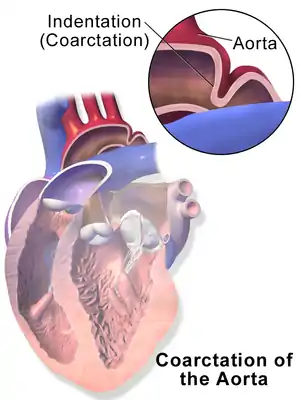

| Illustration depicting coarctation of the aorta | |

Coarctation of the aorta (CoA, CoAo) is a narrowing of the aorta, most commonly just beyond the exit of the left subclavian artery.[3] While present at birth, onset of symptoms may not occur until 1 to 2 weeks after birth with trouble breathing or later in life with high blood pressure in the arms.[2][1] Complications, without treatment, can include coronary artery disease, aortic aneurysm, heart failure, and cerebral vascular disease.[2][1]